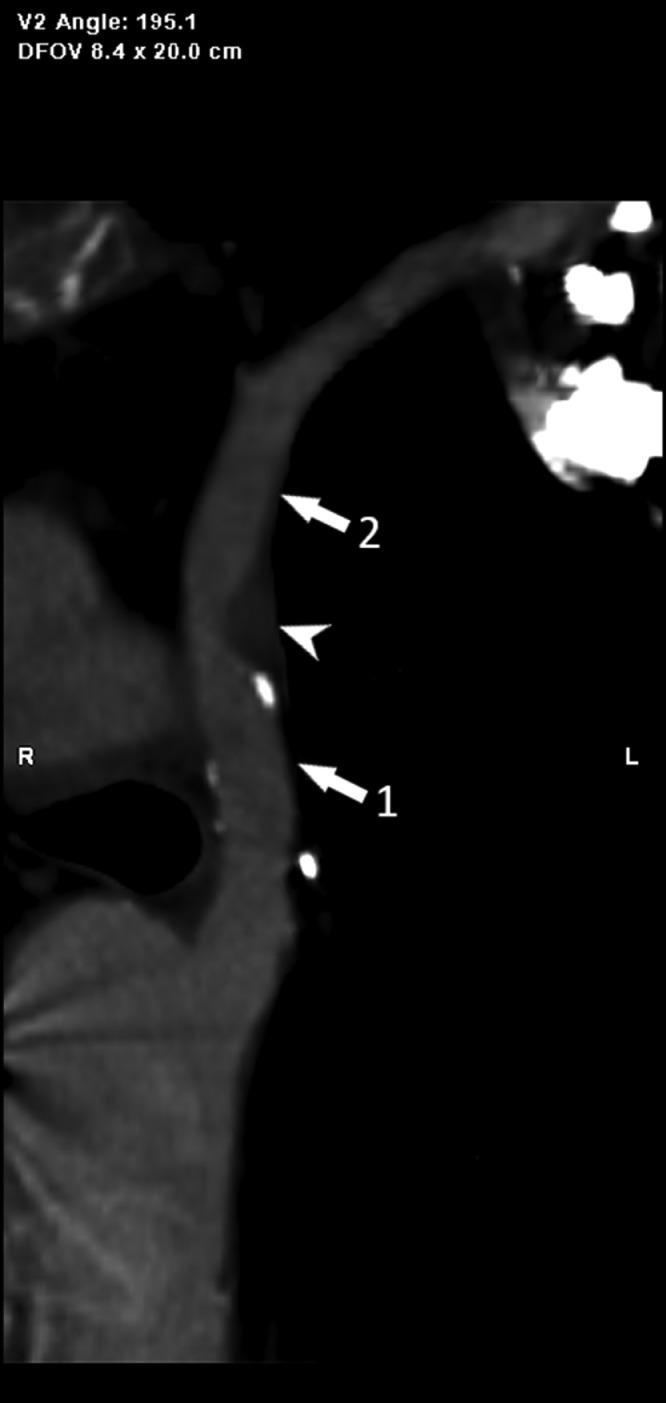

In this paper, we describe a rare case of double aortic arch with dominant right arch with focal narrowing of the distal left arch and descendent aorta's dilatation, associated with pulmonary embolism and left subclavian steal syndrome, found in a 59-year-old woman with a history of dysphagia, chest discomfort, and left arm claudication. Diagnosis of this condition was made with a sub-optimal pulmonary CT-angiography with a combination of characteristic features of double aortic arch and vascular rings. Being aware of these conditions is crucial to avoid misclassification and surgical and endovascular complications.

在本文中,我们描述了一例罕见的双主动脉弓病例,其右弓为主,左弓远端局灶性狭窄,降主动脉扩张,伴有肺栓塞和左锁骨下动脉盗血综合征,该病例见于一名有吞咽困难、胸部不适和左臂间歇性跛行病史的59岁女性。通过结合双主动脉弓和血管环的特征性表现的次优肺部CT血管造影对该疾病进行了诊断。认识到这些情况对于避免误诊以及手术和血管内并发症至关重要。